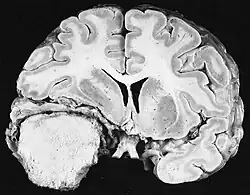

Ionizing radiation

Sources of ionizing radiation include medical imaging, and radon gas. Ionizing radiation is not a particularly strong mutagen.[87] Medical use of ionizing radiation is a growing source of radiation-induced cancers. Ionizing radiation may be used to treat other cancers, but this may, in some cases, induce a second form of cancer.[87] Radiation can cause cancer in most parts of the body, in all animals, and at any age, although radiation-induced solid tumors usually take 10–15 years, and can take up to 40 years, to become clinically manifest, and radiation-induced leukemias typically require 2–10 years to appear.[87] Radiation-induced meningiomas are an uncommon complication of cranial irradiation.[92] Some people, such as those with nevoid basal cell carcinoma syndrome or retinoblastoma, are more susceptible than average to developing cancer from radiation exposure.[87] Children and adolescents are twice as likely to develop radiation-induced leukemia as adults; radiation exposure before birth has ten times the effect.[87]

Ionizing radiation is also used in some kinds of medical imaging. In industrialized countries, medical imaging contributes almost as much radiation dose to the public as natural background radiation. Nuclear medicine techniques involve the injection of radioactive pharmaceuticals directly into the bloodstream. Radiotherapy deliberately deliver high doses of radiation to tumors and surrounding tissues as a form of disease treatment. It is estimated that 0.4% of cancers in 2007 in the United States are due to CTs performed in the past and that this may increase to as high as 1.5–2% with rates of CT usage during this same time period.[93]